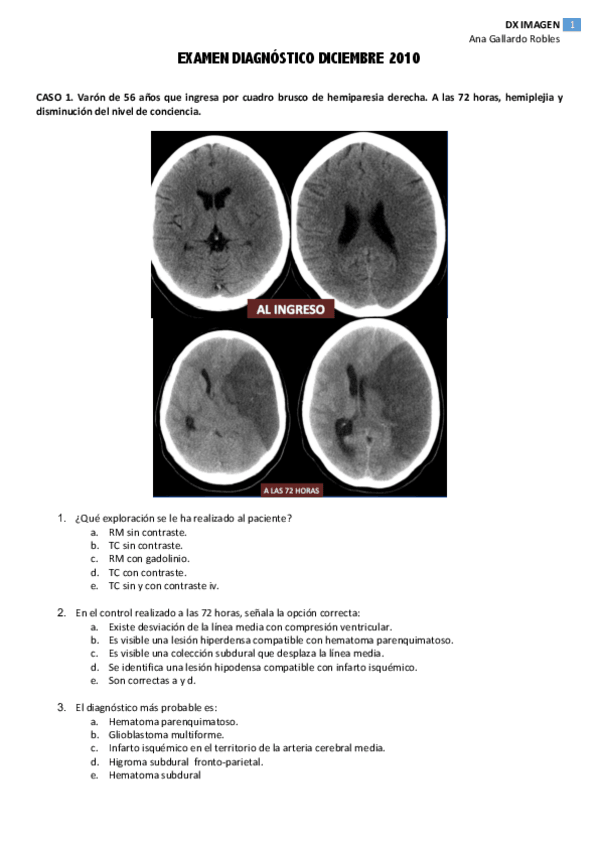

examen 2010 dic.pdf

11 páginas